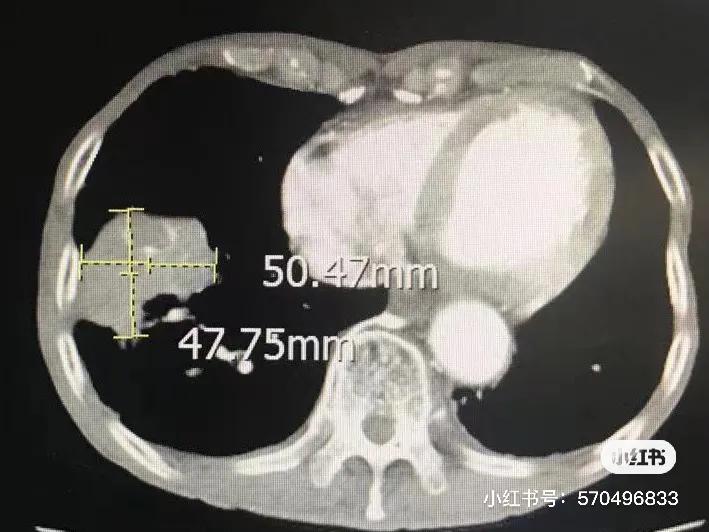

第一次冷冻前CT